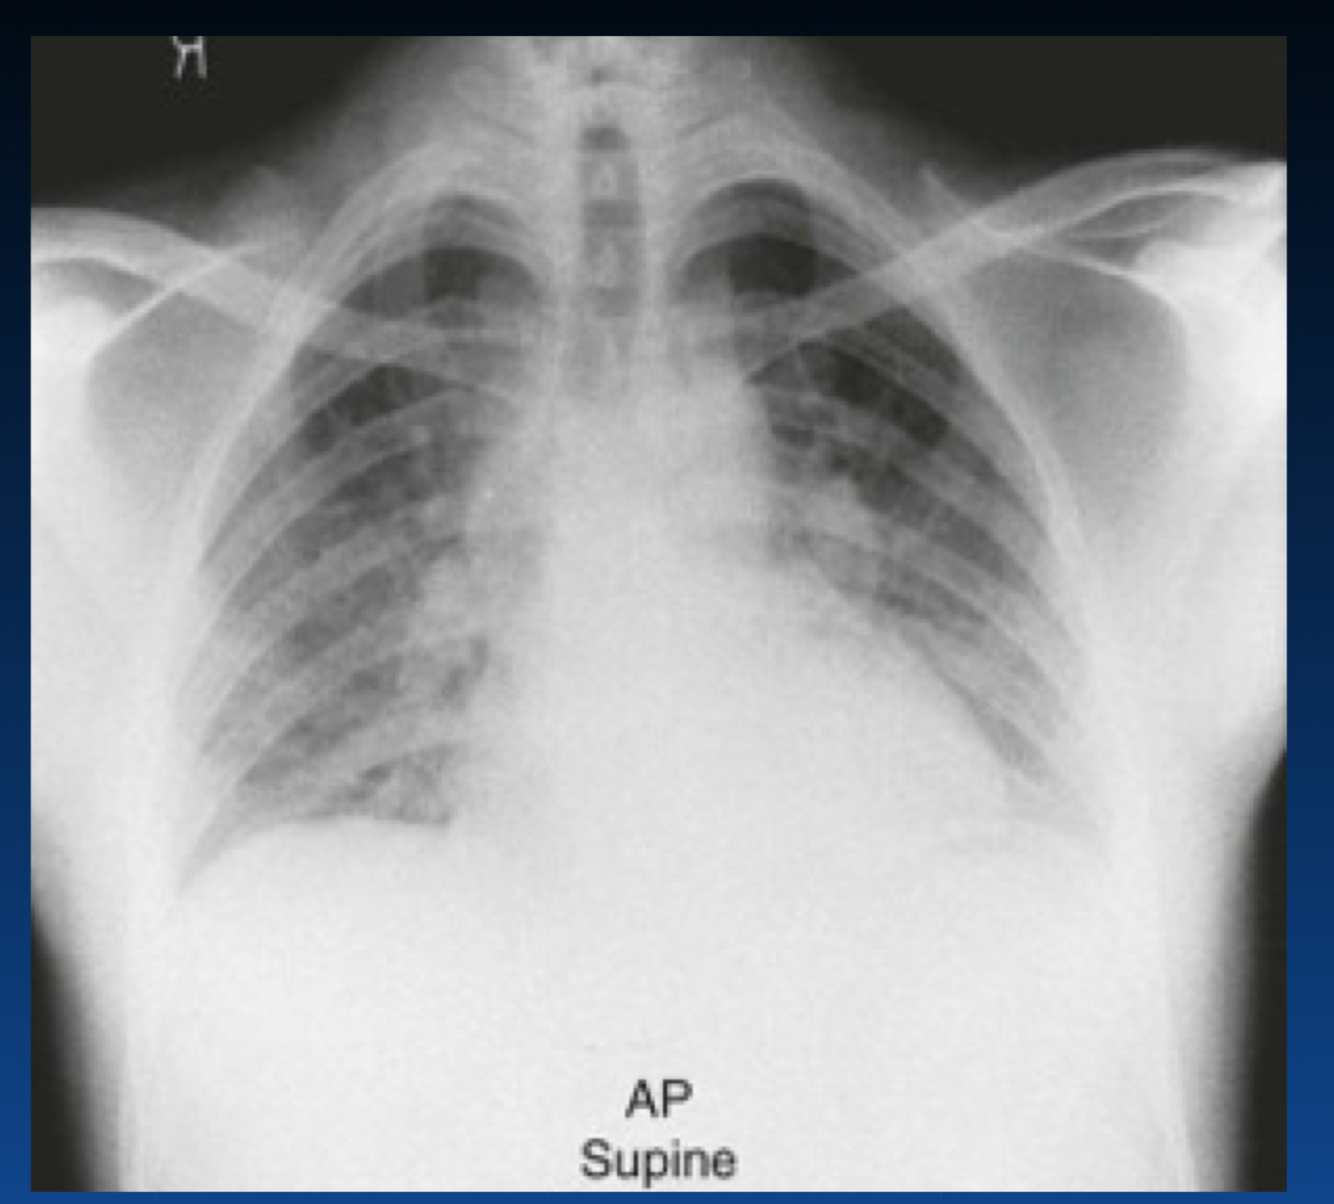

What occurs in this stage of CHF?

The left atrium is enlarged. What sign is the arrow pointing that indicates this?